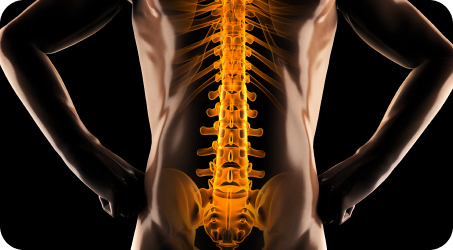

평생 써야 하는 척추, 건강관리의 핵심입니다.

단순히 뼈가 틀어지는 문제가 아닙니다.

척추측만증의 원인은 다양합니다.

척추측만증, 정말 뼈만 보고 치료해야 할까요?